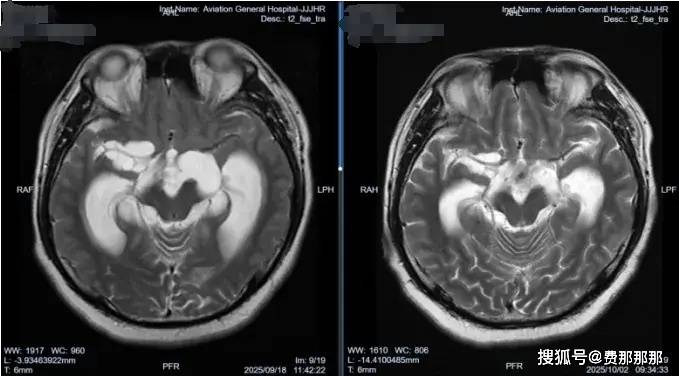

回顾文章开头提到的内蒙古患者图某的情况,他入院后,肖庆教授团队为他做了详细的检查。眼科会诊发现他已有视野缺损和视神经乳突水肿,这表明他的颅内高压已经持续了一段时间,并对视神经造成了损害。他的头颅CT/MR检查显示多发囊性占位,视交叉受压改变,结合他的流行病学史,可以明确脑囊虫病诊断。

术中内镜下可见右侧脑室壁粗糙,广泛炎性黄白色突起肉芽增生——这是既往有过颅内感染的典型表现。肖庆教授更加坚定了之前的判断,进行第三脑室底造瘘,并在基底池内取出数枚囊虫占位,大者外观达2*2cm;同时探查发现基底池内部有多发黄色网状粘连,基底动脉搏动差。